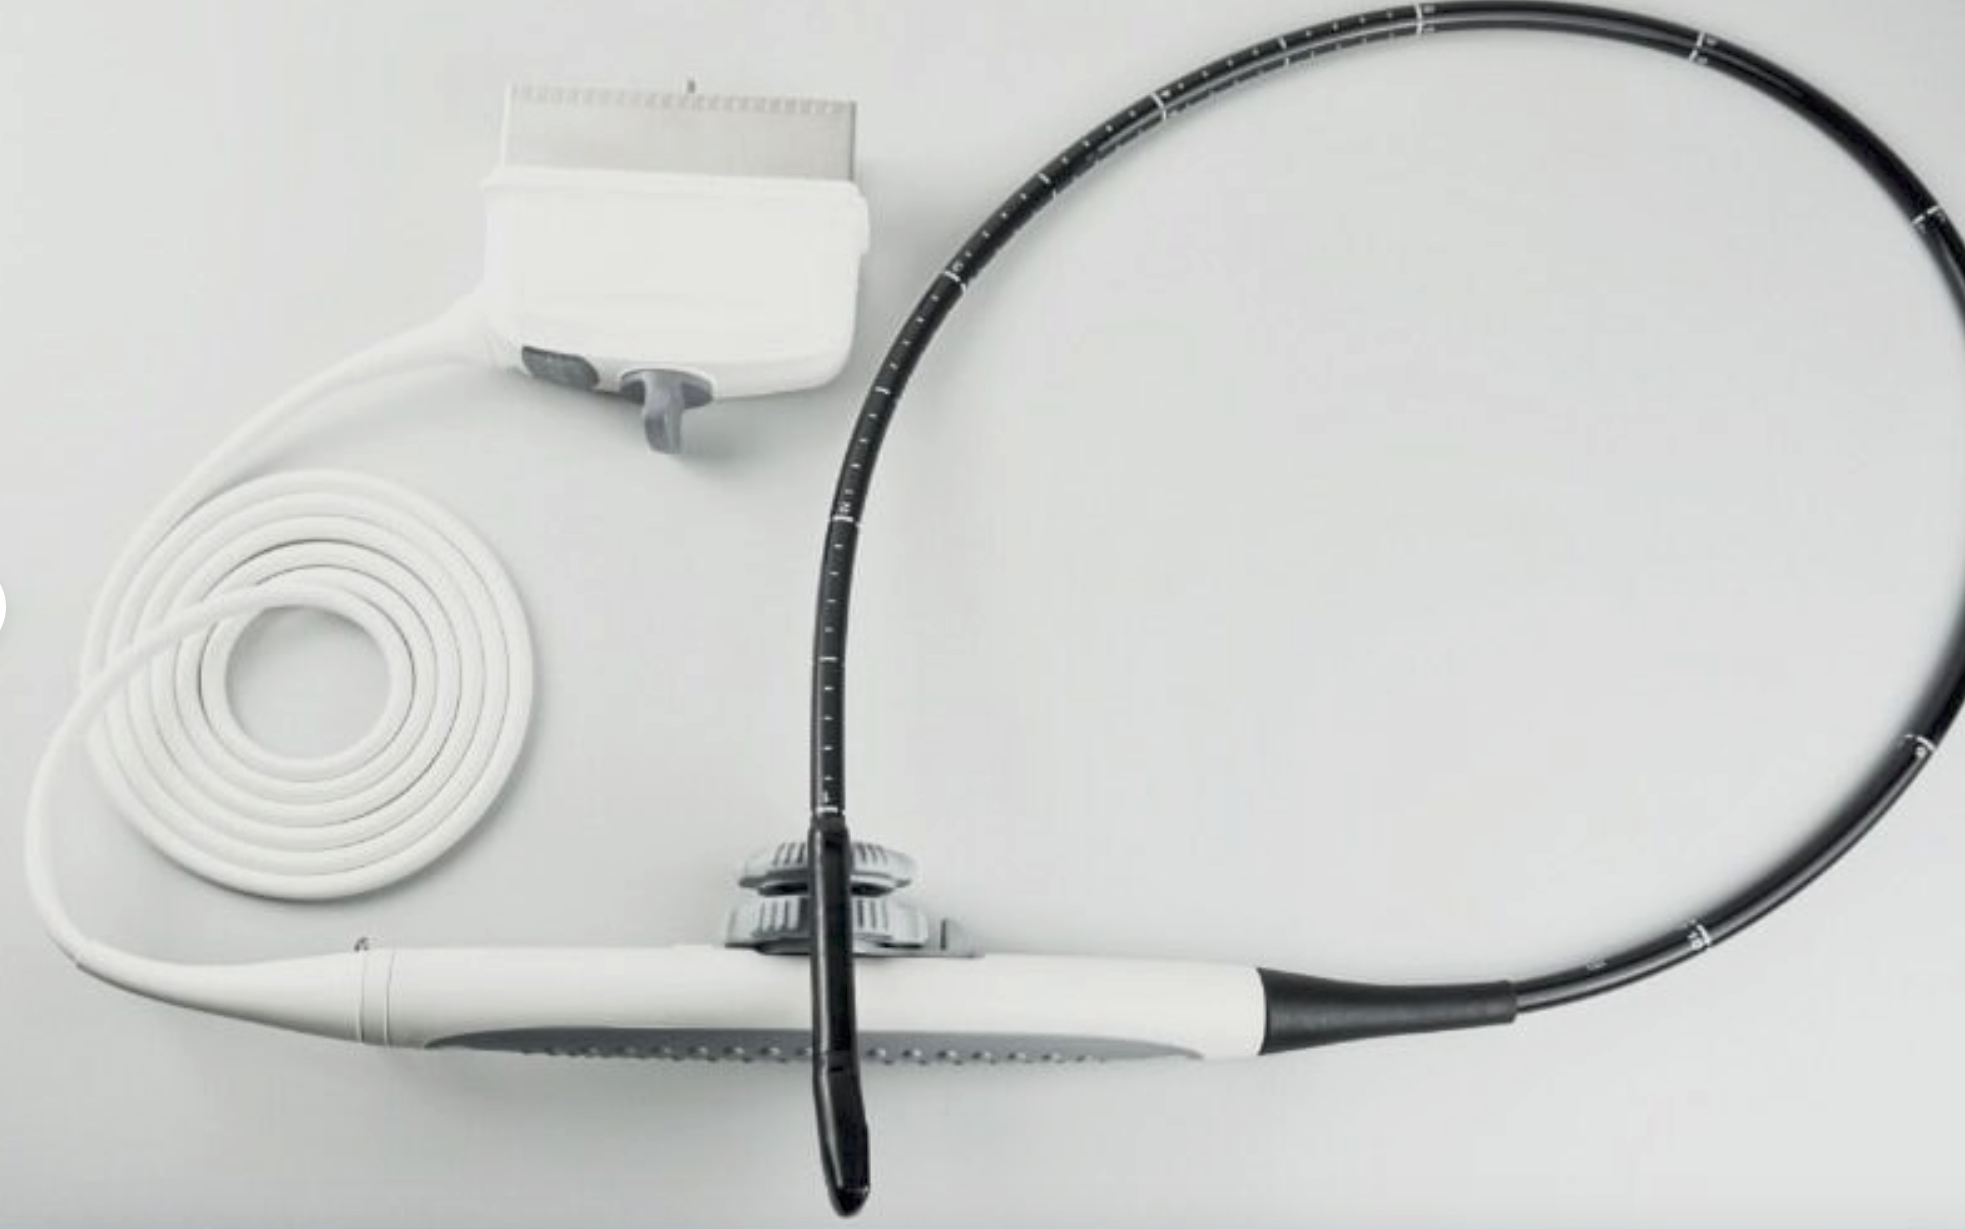

Probe Function: 3.5MHZ convex, abdominal organs

Probe 2: 7.5MHZ Transvaginal probe:gynecologic examination

The Ultrasound Scanner utilizes cutting-edge imaging technology, allowing for detailed and accurate evaluations during pregnancy. With capabilities for both convex and transvaginal scanning, this device provides versatile options for healthcare professionals. It is essential for monitoring fetal development and ensuring the health of both the mother and the unborn child. Doctors can easily select the appropriate probe, enabling them to capture high-resolution images that are critical for diagnosis and treatment.